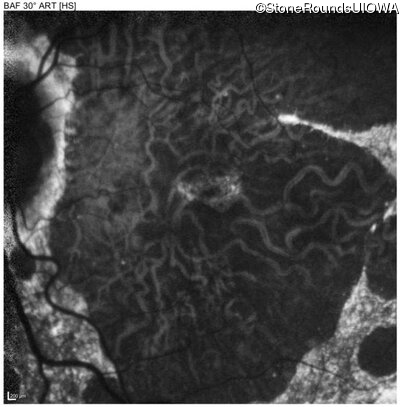

Blue Autofluorescence - Right - 20/20 -3

Exemplar

Blue Autofluorescence - Left - 20/40 +2